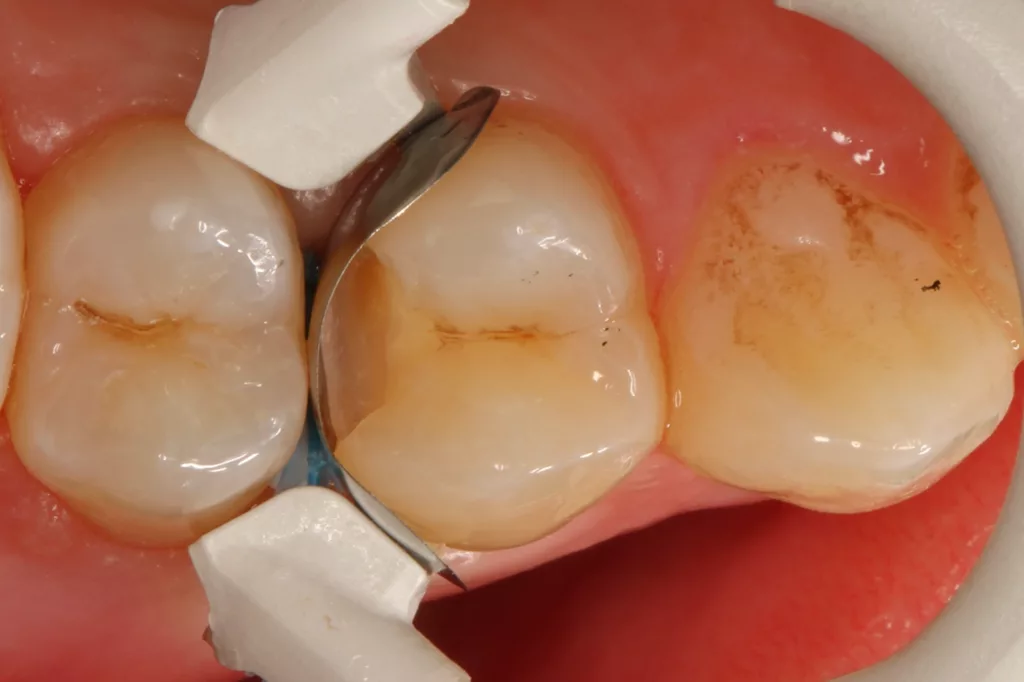

Die 26 Jahre alte Patientin störte sich an der approximalen Lücke zwischen den Zähnen 14 und 15, da sich hier ständig Speisereste impaktierten. Bei der klinischen Inspektion fiel die Initialkaries distal an Zahn 14 auf (Abb. 7). Die Patientin wurde dahingehend beraten, den Spalt mit einer minimalinvasiven Kompositrestauration zu versorgen – bei zeitgleicher Exkavation der Karies an Zahn 14. Nach Exkavation und Präparation des Defektes (der sich als deutlich ausgeprägter präsentierte als anfangs angenommen) erfolgte identisch zu Fall 2 die Ausformung der Kavität mit einer Teilmatrize (Danville ultra thin flex), einem Kunststoffkeilchen (G-Wedge) und der Separation mit einem NiTin-Prämolaren-Spannring (re-invent, Abb. 8).

Teilmatrizensysteme stellen heutzutage die erste Wahl in der Gestaltung anatomischer Kontaktflächen dar [22]: Sie garantieren korrekte anatomische Formen, straffe Approximalkontakte und belastungsoptimiert ausgeformte Randleisten [74–76]. Nach der adhäsiven Vorbehandlung (G2 Universal, GC, total etch) wurde der Defekt identisch zum vorherigen Fall mit dem niedrigviskösen Visalys Bulkflow in einem Zug aufgefüllt und mit der Sondenspitze ausmodelliert (Abb. 9). Die Aushärtung (Elipar Deep Cure) erfolgte erneut standardisiert für jeweils 20 Sek.: einmal okklusal zentral nach Einbringen des Bulkflow-Materials und je einmal als Nachhärtung nach Abnahme der Matrizen-Verschalung aus bukkaler und erneut okklusaler Richtung mit genau auf der Randleiste positioniertem Lichtgerät. So wird mit Sicherheit eine suffiziente Aushärtung des 4 mm tiefen Defektes gewährleistet.

Die Abbildung 10 zeigt das Behandlungsergebnis unmittelbar nach Ausarbeitung und Politur (Diacomp Plus Twist, EVE), die Abbildung 11 bei einer weiteren Kontrolle nach sechs Monaten. In diesem Kontrolltermin wurden dann im routinemäßigen, zwei- bis dreijährigen Intervall Bissflügelröntgenaufnahmen zur Kariesdiagnostik angefertigt. Auf der Röntgenaufnahme zeigt sich die neue Visalys-Bulk-Flow-Restauration als randdicht, anatomisch korrekt geformt und ausreichend röntgenopak (Abb. 12). Die Schmelzläsion mesial an den Zähnen 15 und 16 erschien nicht therapiebedürftig, da die Oberfläche intakt war, wohl aber die versteckte Dentinläsion distal an dem Zahn 15. Der Defekt wurde in einem weiteren Termin identisch mit denselben Materialkombinationen und identischem Polymerisationsprotokoll versorgt (Abb. 13 bis 15).